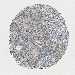

CERVICAL CANCER - Protein expressioni

A mouse-over function shows sample information and annotation data. Click on an image to view it in a full screen mode. Samples can be filtered based on level of antibody staining by selecting one or several of the following categories: high, medium, low and not detected. The assay and annotation is described here.

Note that samples used for immunohistochemistry by the Human Protein Atlas do not correspond to samples in the TCGA dataset.

Antibody stainingi

Antibody staining in the annotated cell types in the current human tissue is reported as not detected, low, medium, or high, based on conventional immunohistochemistry profiling in selected tissues. This score is based on the combination of the staining intensity and fraction of stained cells.

Each image is clickable and will lead to virtual microscopy that enables deeper exploration of all samples and also displays staining intensity scores, fraction scores and subcellular localization as well as patient and tissue information for each sample.

Antibody HPA017283

Staining

High

Medium

Low

Not detected

Intensity

Strong

Moderate

Weak

Negative

Quantity

>75%

75%-25%

<25%

None

Location

Nuclear

Cytoplasmic/membranous

Cytoplasmic/membranous,nuclear

Squamous cell carcinoma, NOS

Adenocarcinoma, NOS